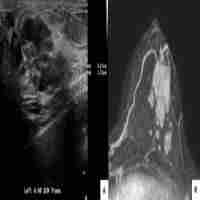

| Description | Introduction: Although treatment of bone tumors is multidisciplinary, the complete surgical resection of bone tumors remains the mainstay of the treatment. Patient-specific instruments (PSI) are personalized tools, which help the surgeon to perform tumor resections accurately. The aim of this study is to evaluate how precise the planned resection can be intraoperatively executed with the use of PSI. Patients and Methods: Eleven patients who underwent a resection of bone tumor using PSI were analyzed. A preoperative model of the tumor and the affected bone was created from acquired CT scans and MRI. After defining the resection planes, PSI were produced by a 3D printer. The resected piece of bone was scanned and imported in the original planning model enabling the assessment of the distance between the planned resection plane and the realized osteotomy in every direction. Results: In overall, the combined error of an osteotomy ranges from 0.74 ± 0.96 mm to 3.60 ± 2.46 mm. The average errors observed in situations with one resection plane (simple osteotomy) are lower than in complex curved osteotomies with multiple planes, in which we also found a greater variance. Conclusion: 3D planned bone tumor resections using PSI show promising results for precise resection at different anatomical regions. Even if the found error range in this series is slightly higher than reported, PSI remain a valuable tool to facilitate complex bone tumor resections. |